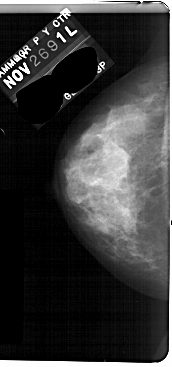

A_1736_1.LEFT_CC

LEFT_CC LINES 5491 PIXELS_PER_LINE 2566 BITS_PER_PIXEL 12 RESOLUTION 43.5 NON_OVERLAY